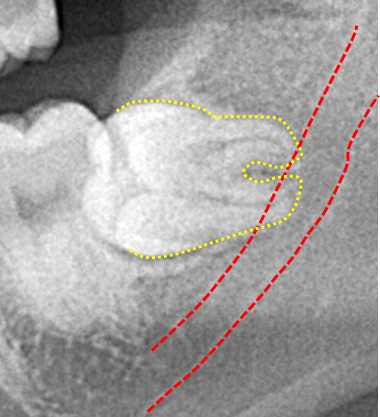

パノラマレントゲン撮影で得られる画像は2次元のため、下顎神経の走行や上顎洞と歯の詳細な位置関係を知るのが難しい場合があります。

CT像では歯の生え方や神経の走行、上顎洞との位置関係などを3次元で確認することができるため、より正確な診断が可能です。主治医が総合的に判断しCT撮影を提案された場合はより安全な抜歯のために受けることをお勧めいたします。また患者様のご希望でも撮影は行いますのでお申しつけください。

親知らずの歯根の先端と下顎神経が近接している場合は2回に分けて抜歯を行うことがあります。まず、親知らずを2分割して頭の部分を抜きます。その後しばらく期間をおいて、のこる歯根の部分が頭を抜いたスペースに移動したのを確認して抜きます。

このように2回に分ける事で安全な抜歯が可能です。

下顎骨には歯や骨へ栄養を送る血管(下歯槽動静脈)と知覚を司る神経(下歯槽神経)が通る下顎管があります。親知らずの根の先とその下顎管が近接していることから、抜歯処置によって麻痺が起こる可能性があります。基本的には神経を切らない限り、完全に知覚を失うことはないですが、抜歯はてこの原理で行われ、横向きに生えた親知らずの根尖によりその力が下顎管へ刺激され神経麻痺が起こるとされています。